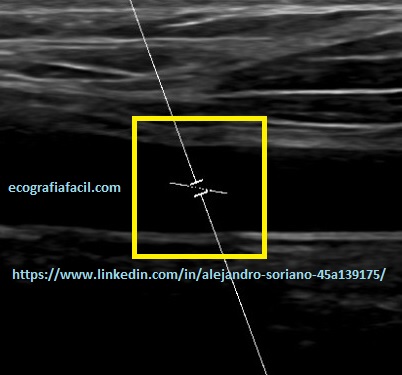

- Volumen de la muestra: se situará en el centro del vaso y deberá tener un tamaño acorde a éste.

- Tendremos que tener un comando en la botonera o en el submenú digital que se denomine «muestra» y con él regular convenientemente el tamaño de ésta.

- Ángulo: la línea de la angulación debe quedar paralela a las paredes del vaso para obtener datos precisos.

- Disponemos un comando en la botonera o en el submenú digital que se denomine «Angle o Ángulo» y con él regular convenientemente el tamaño de ésta.

Como vemos en las tres imágenes con distintas angulaciones obtendremos un espectro bastante decente pero no en todos los casos obtendremos datos suficientemente fiables.

En la imagen 10 tenemos un ángulo inferior a 60º pero la línea de la angulación no es paralela.